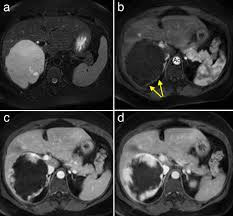

Η διάγνωση βασίζεται κυρίως στις απεικονιστικές μεθόδους:

• Υπερηχογράφημα άνω κοιλίας

• Αξονική τομογραφία με σκιαγραφικό

• Μαγνητική τομογραφία, η οποία θεωρείται η πλέον ειδική μέθοδος